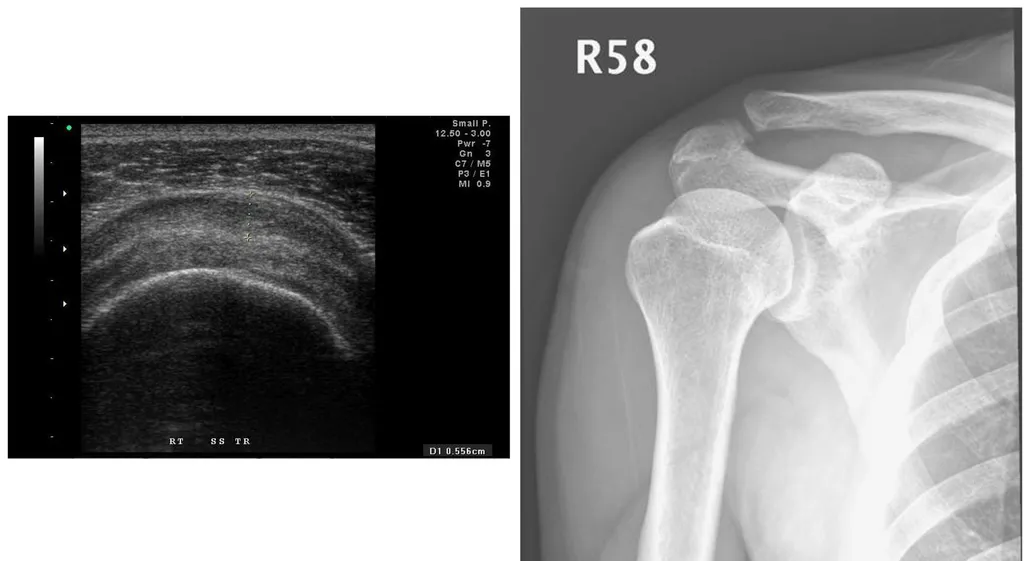

【106-1 醫學(六) 第73題】51歲男性病人,右側肩膀疼痛,且轉動受限。超音波及X光片檢查如圖,最可能的診斷為何?

詳解

破題關鍵

這題的解題核心在於辨識超音波影像中肩峰下滑囊的異常增厚,同時結合X光片排除其他骨骼或鈣化問題,指向滑囊炎。

選項拆解